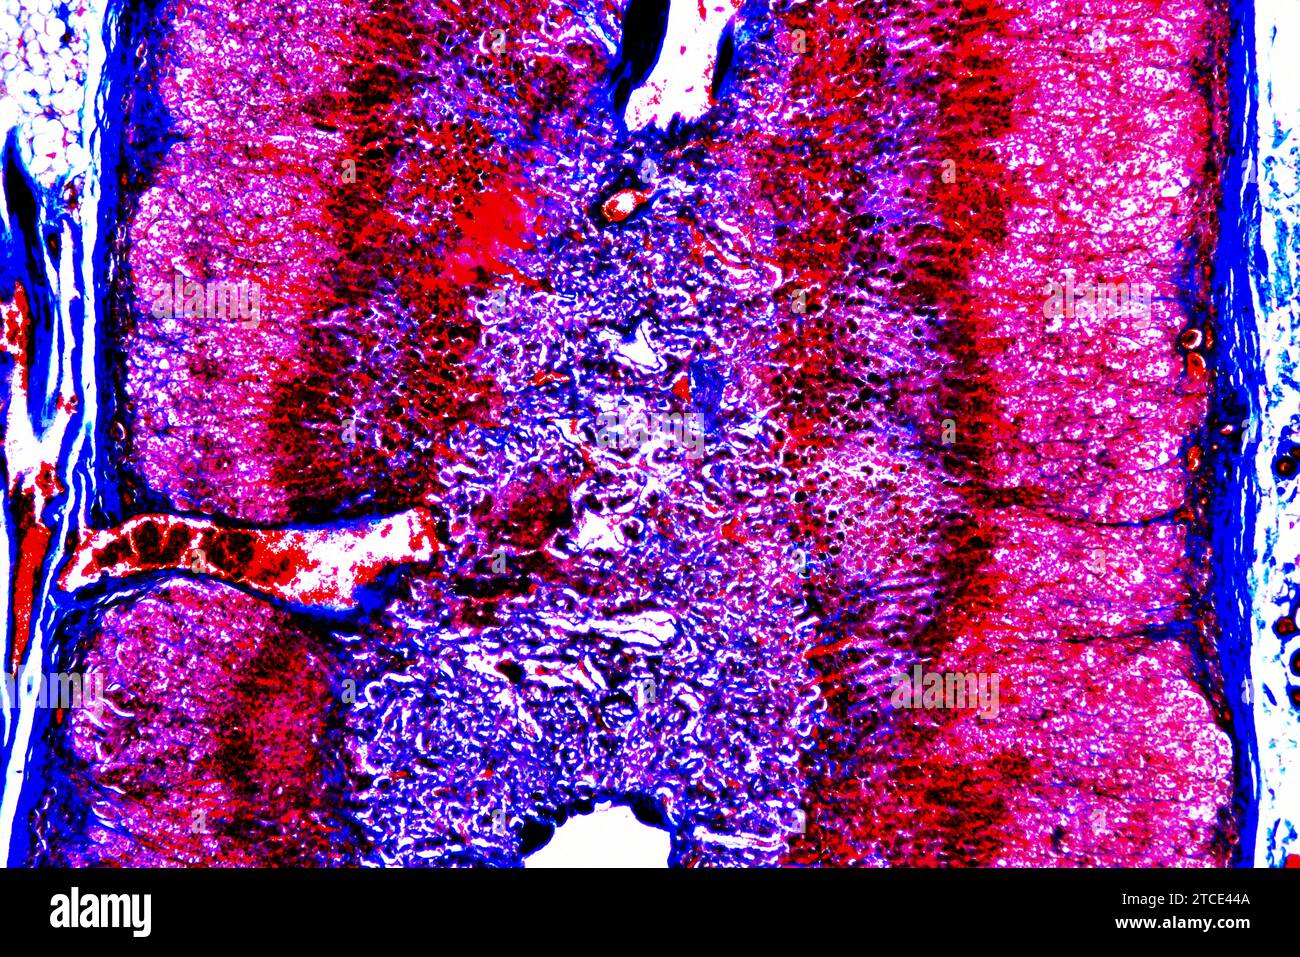

From www.alamy.com

Human adrenal or suprarenal gland showing fibrous capsule, zona What Is Zona Glomerulosa the cells of the outermost region of the adrenal cortex, the zona glomerulosa, are smaller and more rounded and contain. 63 rows the zona glomerulosa is responsible for the production of aldosterone, the zona fasciculata for the production of. the zona glomerulosa is the narrow outer layer of the suprarenal cortex. the adrenal cortex comprises three. What Is Zona Glomerulosa.